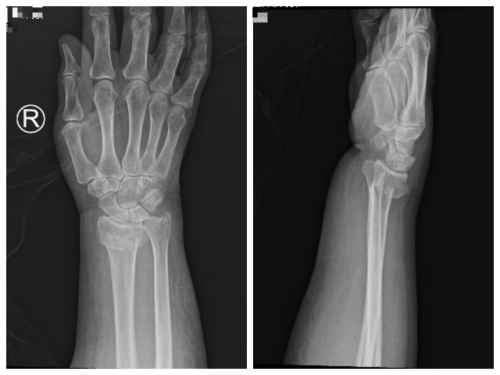

术前

患者米某因外伤导致右桡骨远端骨折。面对患者病情,骨科主任国华带领医疗团队展开详尽的病例讨论:传统治疗中,手法复位后石膏固定虽操作便捷,但该部位骨折稳定性不足,后期易发生移位;而切开复位内固定(植入钢板螺钉)虽固定牢固,却存在手术创伤大、遗留较长疤痕等弊端,而且患者明确表示不接受切开复位方案。经综合评估,医疗团队提出外固定支架固定方案——既能确保骨折断端稳定性,又能避免切开手术带来的较大创伤,同时满足患者对美观及功能恢复的需求,有效降低骨折术后并发症风险。